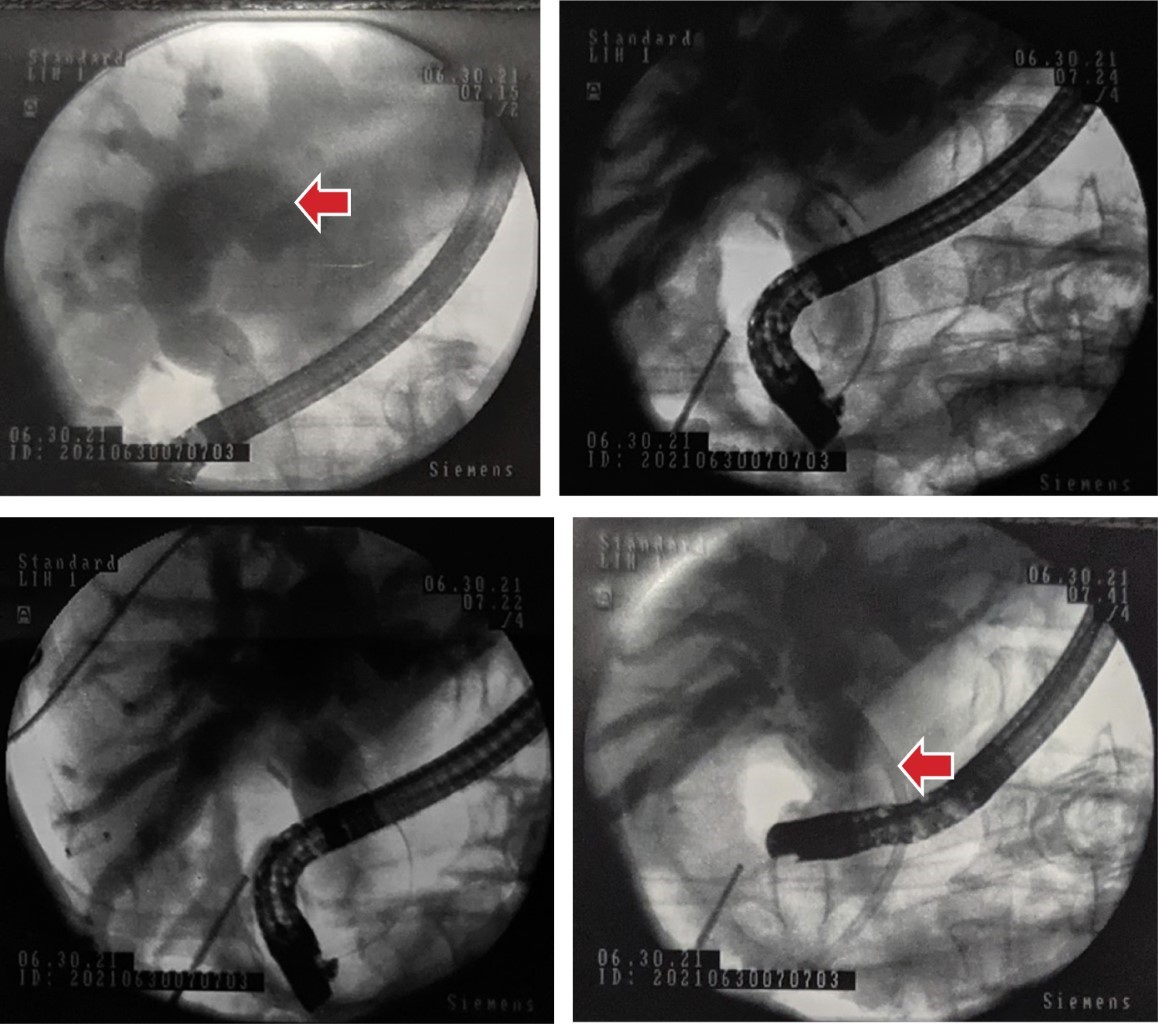

Durante el procedimiento quirúrgico se encuentra vesícula edematosa aumentada de tamaño con contenido purulento, pared engrosada de hasta 8 mm y segmentos de necrosis en su superficie, se observa dilatación del conducto cístico hasta 25 mm (Figura 2). Se procede a introducir duodenoscopio de visión lateral en tiempo transoperatorio hasta la segunda porción del duodeno, observando papila hipertrófica con ausencia de salida de bilis, se canula esfínter de Oddi en el primer intento y se opacifica de manera selectiva la vía biliar con medio de contraste observando dilatación importante de la vía intra y extrahepática, con colédoco tortuoso que llega a medir hasta 25 mm, por debajo de la unión de los conductos hepáticos derecho e izquierdo. En la unión del conducto cístico se observa una estenosis concéntrica de consistencia dura franqueable con la guía (Figura 3). Se realizan tres barridos con balón extractor obteniendo sólo detritus biliares con hemorragia al paso por el sitio de la estenosis. Se realiza cepillado biliar para ser procesado por patología y esfinterotomía de 20 mm, se decide colocar prótesis biliar Cotton-Leung® de 10 × 10 Fr y se retira la vesícula biliar (Figura 4).

Figura 3